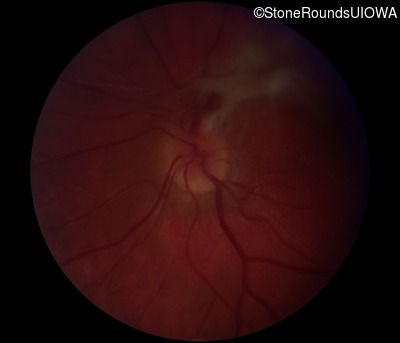

Fundus Photography - Right - 20/125 -2 sc

Exemplar